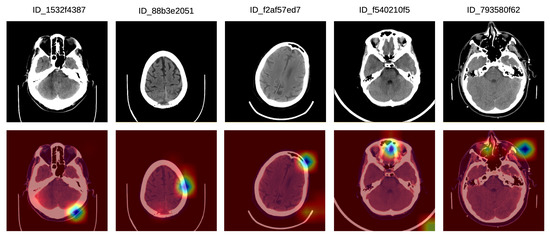

- We provide interpretations explaining the decisions of our model.